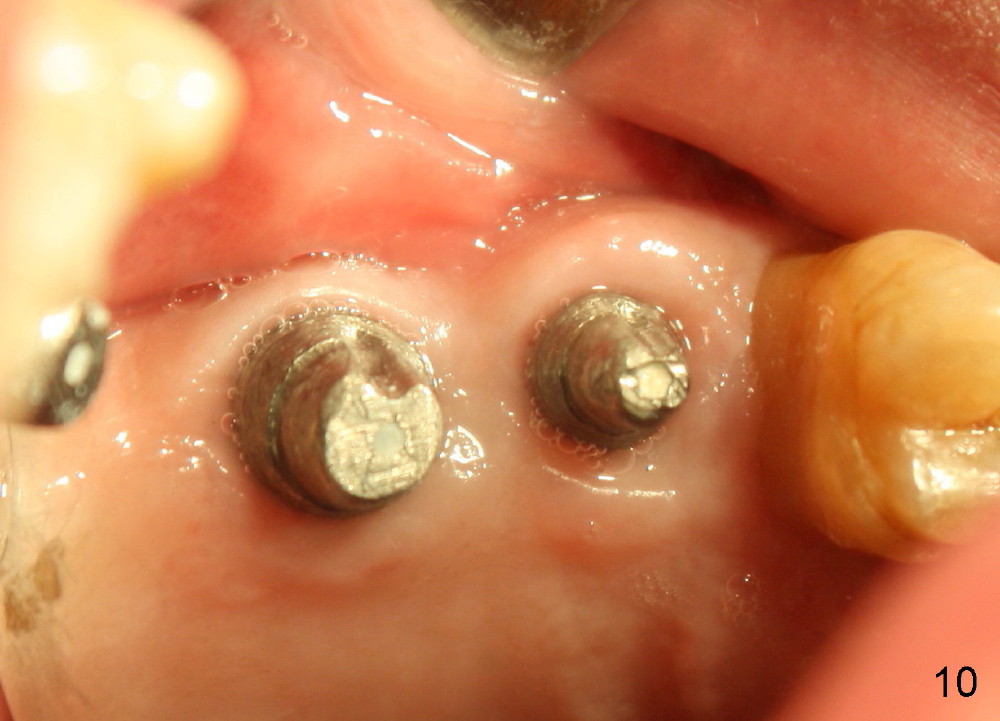

Bone graft remains in place 2 months postop (Fig.7 arrowheads); its density increses 4 months postop (Fig.8). The gingiva around the implant and abutment at the site of #14 is healthy (Fig.9 (4 months postop before final impression);10 (5 months postop immediately before final cementation)).